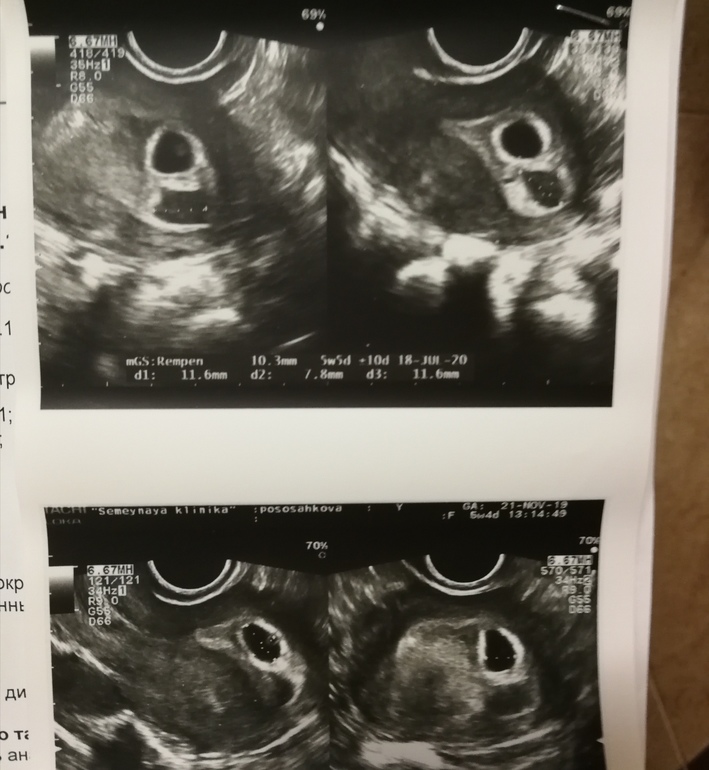

Первое узи. 5-6 нелель

Как думаете, есть вероятность что там 2 живых ляльки или одна?

Узистка очень долго смотрела и написала что все под вопросом со 2 малышем.

Ого! У вас сразу два❤️❤️ Как я поняла одно плодное яйцо всегда будет чуть больше второго. У вас какой размер? Написали?

Написали только по 1. Мол только он хорошо выглядит. 12.1 *7.3 *. 7.9

По второму неопределённое.

Под вопросом